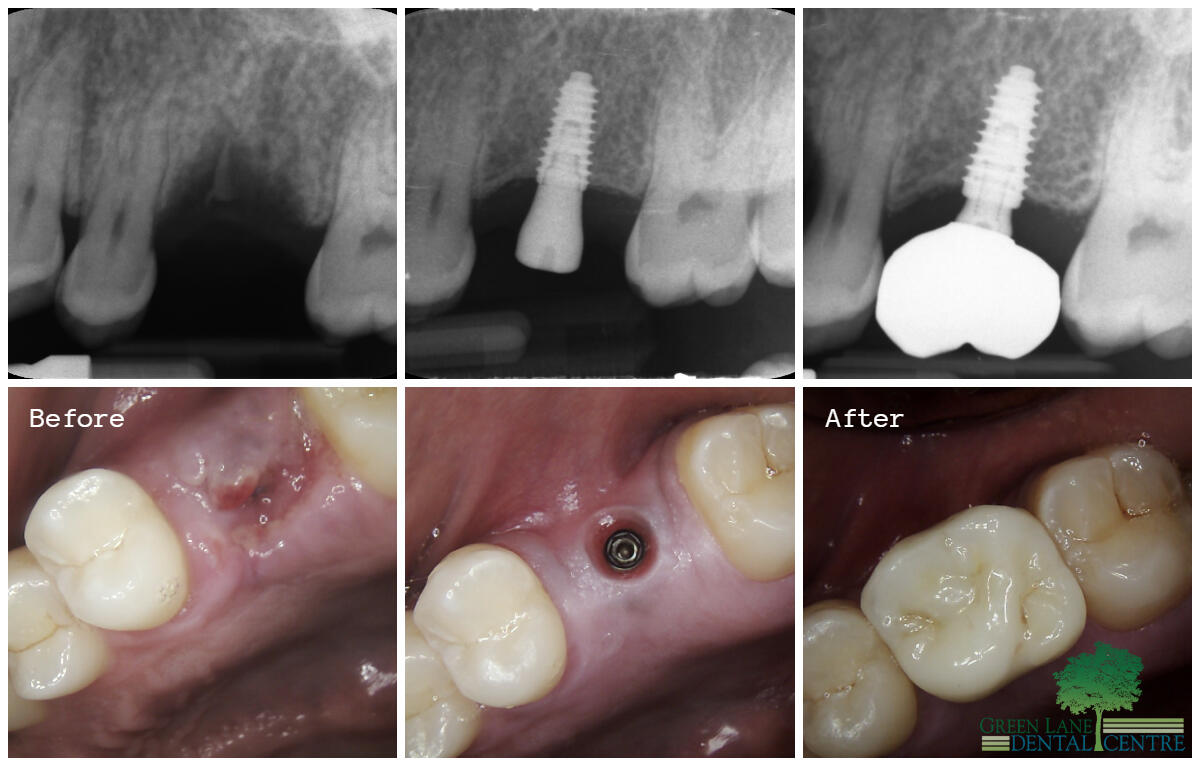

Smile Gallery